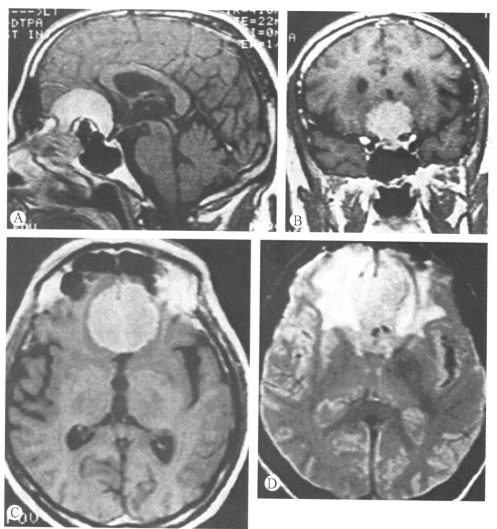

59歲男性嗅溝腦膜瘤患者,3年來輕度人格改變和智能障礙。磁共振:A.矢狀位(T1)增強像:中線平面顯示腫瘤的前后和上部范圍。有一種不常見的骨質(zhì)改變,氣竇向顱底腫瘤擴展。腫瘤的后下緣位于鞍結節(jié)下,雙側(cè)視神經(jīng)間。腫瘤的后表面有腦脊液池。腫瘤的前下緣侵犯篩板區(qū)。B.冠狀位(T1)增強像:腫瘤后緣平面顯示腫瘤片位于雙側(cè)頸內(nèi)動脈間視神經(jīng)上。其他冠狀位像顯示腫瘤外側(cè)部沒有侵入氣竇。C.軸位(T1)增強像:確定腫瘤的外側(cè)邊界。腫瘤周圍有水腫或膠質(zhì)反應。D.軸位(T2)未增強像:確定腫瘤鄰近組織的水腫范圍。大腦前動脈的A2段鄰近腫瘤包膜。術中將大腦前動脈A2段從腫瘤包膜上后部通過薄層膠質(zhì)組織分離開,在后部包膜的中部,動脈位于腦脊液池中,有小動脈分支硫松附著于腫瘤包膜。全切除腫瘤,病人完全恢復。